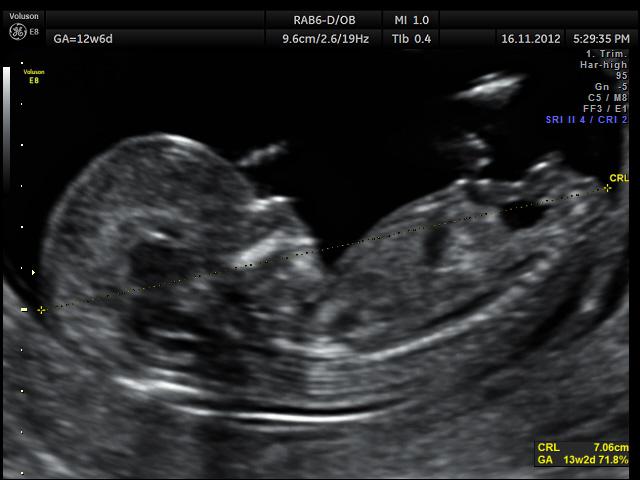

Bambini: Dal concepimento alla morte. Su Tik Tok i bambini sono una vera e propria risorsa, i neogenitori già dalle prime settimana di ritardo di ciclo mestruale, cominciano a postare frasi d’amore infinito nei confronti dell’eventuale nascituro, segue foto e video nel bagno decoratissimo del test di gravidanza con canzone dolcissima, segue baby shower con finta sorpresa dei genitori e di amici e parenti che applaudono, si baciano, si congratulano. Eserciti di professionisti si inventano i modi più estrosi di comunicare al mondo il sesso del nascituro (palloncini, mongolfiera, cascata di petali, colombe colorate, elicottero che sorvola il cielo con la scritta “Sara Lei? o Sarà Lui? Dopo il Baby shower l’ecografia del piccolo essere sarà mostrata in lungo e in largo, ogni acquisto sarà discusso, deciso, comprato e registrato, i pensieri dei nonni, degli zii e degli amici più cari allieteranno l’allestimento della stanzetta. La nascita è un tripudio, rose, anelli, diamanti e lo stesso piccolino/a inquadrati e ripresi al ritmo di un video ogni quarto d’ora. Non parliamo del battesimo e del primo compleanno, altro che album di fotografie dei miei tempi, qui c’è da farsi venire l’esaurimento nervoso. Il destino dei pargoletti un po’ cresciuti è già segnato nel loro genere, le femminucce diventano piccole donne (non nel senso del romanzo) e vengono vestite, pettinate e persino truccate come dive e starlette, le piccoline sollecitate da mamma e papà cantano canzoncine lezzose, o si inventano buffi modi di dire in camerette che fanno impallidire la stessa Barbie. La vita per i maschietti è un po’ più movimentata, stanno con i papà che li portano al lavoro, in campagna, a cavalcare piccoli pony, a portare il mangime a polli, oche, allevati nella fattoria dei nonni che sorridono felici vedendo l’intelligenza del nipotino. Talvolta i bimbi sono talmente stanchi di essere ripresi che si lanciano in capricci e monellerie peggio di Gian Burrasca, oppure si ammutoliscono e cercano con lo sguardo la pietà dell’amato genitore che nonostante i pianti e i lamenti continua a riprendere.